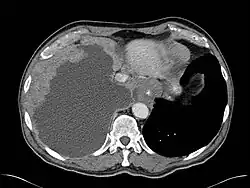

Mesothelioma Overview

Pathology

- Sarcomatous

- Epithelial (best prognosis of 3 subtypes)

- Mixed